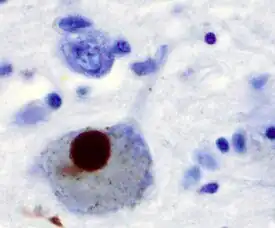

The main pathological characteristics of PD are cell death in the brain's basal ganglia (affecting up to 70% of the dopamine-secreting neurons in the substantia nigra pars compacta by the end of life).[65] In Parkinson's disease, alpha-synuclein becomes misfolded and clump together with other alpha-synuclein. Cells are unable to remove these clumps, and the alpha-synuclein becomes cytotoxic, damaging the cells.[66][67] These clumps can be seen in neurons under a microscope and are called Lewy bodies. Loss of neurons is accompanied by the death of astrocytes (star-shaped glial cells) and an increase in the number of microglia (another type of glial cell) in the substantia nigra.[68] Severity of progression of the parts of the brain affected by PD can be measured with Braak staging. According to this staging, PD starts in the medulla and the olfactory bulb before moving to the substantia nigra pars compacta and the rest of the midbrain/basal forebrain. Movement symptom onset is associated when the disease begins to affect the substantia nigra pars compacta.[69]

One mechanism causing brain cell death results from abnormal accumulation of the protein alpha-synuclein bound to ubiquitin in damaged cells. This insoluble protein accumulates inside neurons forming inclusions, known as Lewy bodies.[65][71] These bodies first appear in the olfactory bulb, medulla oblongata and pontine tegmentum; individuals at this stage may be asymptomatic or have early nonmotor symptoms (such as loss of sense of smell or some sleep or automatic dysfunction). As the disease progresses, Lewy bodies develop in the substantia nigra, areas of the midbrain and basal forebrain, and finally, the neocortex.[65] These brain sites are the main places of neuronal degeneration in PD, but Lewy bodies may be protective from cell death (with the abnormal protein sequestered or walled off). Other forms of alpha-synuclein (e.g. oligomers) that are not aggregated into Lewy bodies and Lewy neurites, may in fact be the toxic forms of the protein.[72][71] In people with dementia, a generalized presence of Lewy bodies is common in cortical areas. Neurofibrillary tangles and senile plaques, characteristic of Alzheimer's disease, are uncommon unless the person has dementia.[68]

In 1912, Frederic Lewy described microscopic particles in affected brains, later named Lewy bodies.[169] In 1919, Konstantin Tretiakoff reported that the substantia nigra was the main cerebral structure affected, but this finding was rejected until it was confirmed by further studies published by Rolf Hassler in 1938.[169] The underlying biochemical changes in the brain were identified in the 1950s, due largely to the work of Arvid Carlsson on the neurotransmitter dopamine and Oleh Hornykiewicz on its role on PD.[172] In 1997, alpha-synuclein was found to be the main component of Lewy bodies by Spillantini, Trojanowski, Goedert, and others.[71]